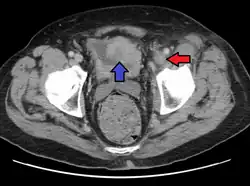

| A person with a two hour history of phlegmasia cerulea dolens (left leg, right side of image) |